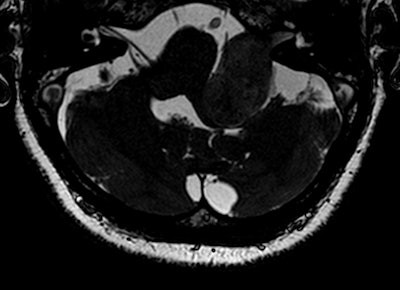

The problem has arisen because MRI has a central role in evaluating vestibular schwannoma in first diagnosis and follow-up, with contrast-enhanced T1-weighted images considered to be the gold standard for tumor assessment.

Most of the controversies regarding the use of gadolinium focus on the primary diagnosis -- rather than follow-up and post-treatment -- of vestibular schwannoma, which is a benign intracranial tumor of the myelin-forming cells of the vestibulocochlear nerve in the internal auditory canal next to the brain. Patients may present with sensorineural hearing loss, tinnitus, and balance problems, but only a small percentage of people with these symptoms will have vestibular schwannoma, explained Dr. Berit Verbist, a neuro and head and neck radiologist at Leiden University Medical Centre in the Netherlands.